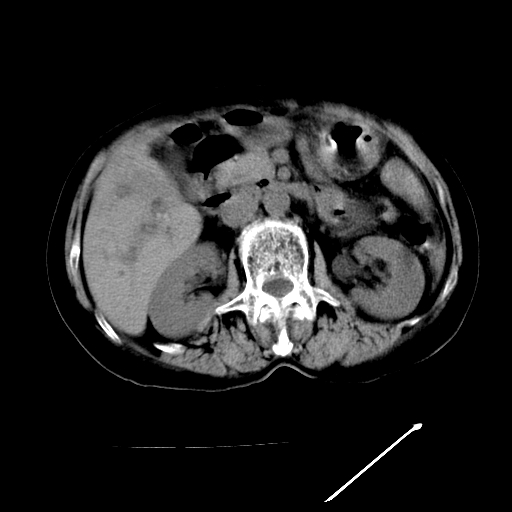

以下是引用随光逐影在2009-4-7 8:21:00的发言:[br]肝内外胆管多发性结石并肝内外胆管扩张;胆系感染。